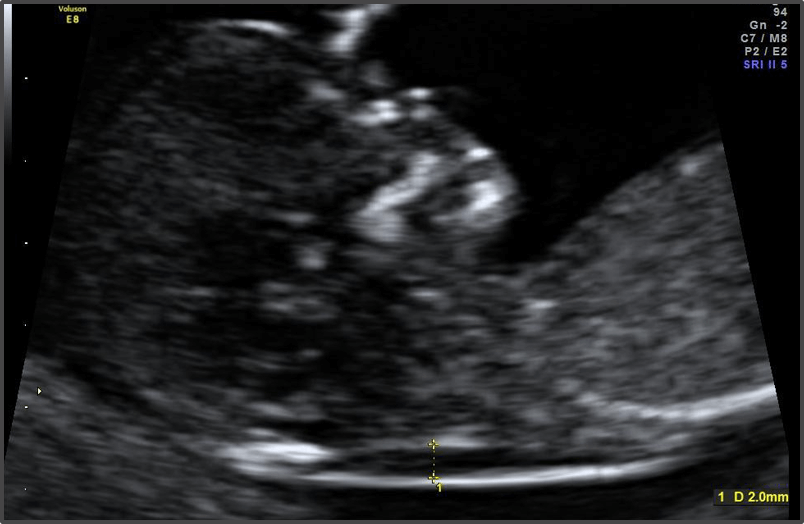

Baby is the size of Plum

Approx Baby Weight: 14g

Approx Baby Size: 5.4 cm

Baby Development

Eyelids are nearly closed, and tiny fingernails are forming.